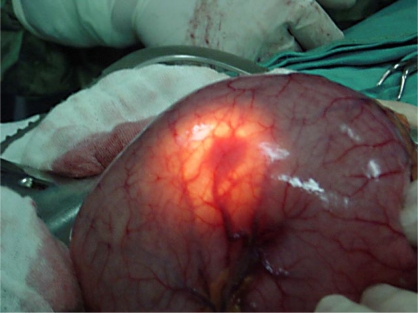

Total gastrectomy specimen. Brown arrows – Multiple gastric stromal tumors (Courtesy Dr. V. Penopoulos)